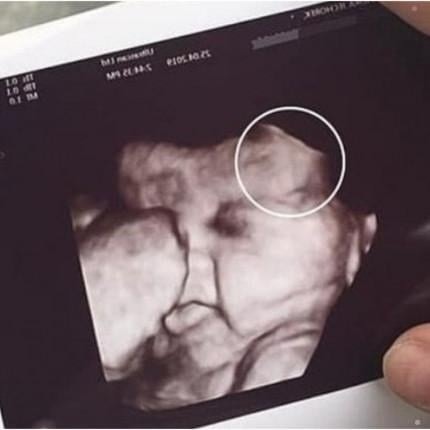

A routine prenatal checkup took an unexpected turn for one mother after she grew visibly anxious during her daughter’s ultrasound appointment. According to witnesses at the clinic, the mother had accompanied her daughter for support but became increasingly uneasy as the technician prepared to reveal the scan. What was supposed to be a joyful moment quickly shifted into uncertainty when the medical staff paused to take a closer look at the monitor.

The technician, maintaining calm professionalism, informed the family that the image had shown something unusual that required further evaluation. While they did not immediately disclose details, the brief silence in the room left both mother and daughter unsettled. Staff assured them that unclear images are common—ultrasounds can sometimes capture shadows, angles, or movements that look concerning but turn out to be harmless upon review.

Doctors later explained that the initial scan had displayed an unexpected shape next to the developing baby, prompting the need for additional imaging. After a follow-up exam, they determined it was a benign artifact—a harmless visual distortion caused by the baby’s position and the machine’s angle. The clarification brought immense relief to both women, who had been preparing themselves for difficult news.

The family later expressed gratitude to the clinic for handling the situation with care and transparency. Medical specialists remind expecting parents that unusual ultrasound images are not uncommon and often resolve with clearer scans. The incident underscores the emotional weight of prenatal appointments and the importance of compassionate communication in moments of uncertainty.